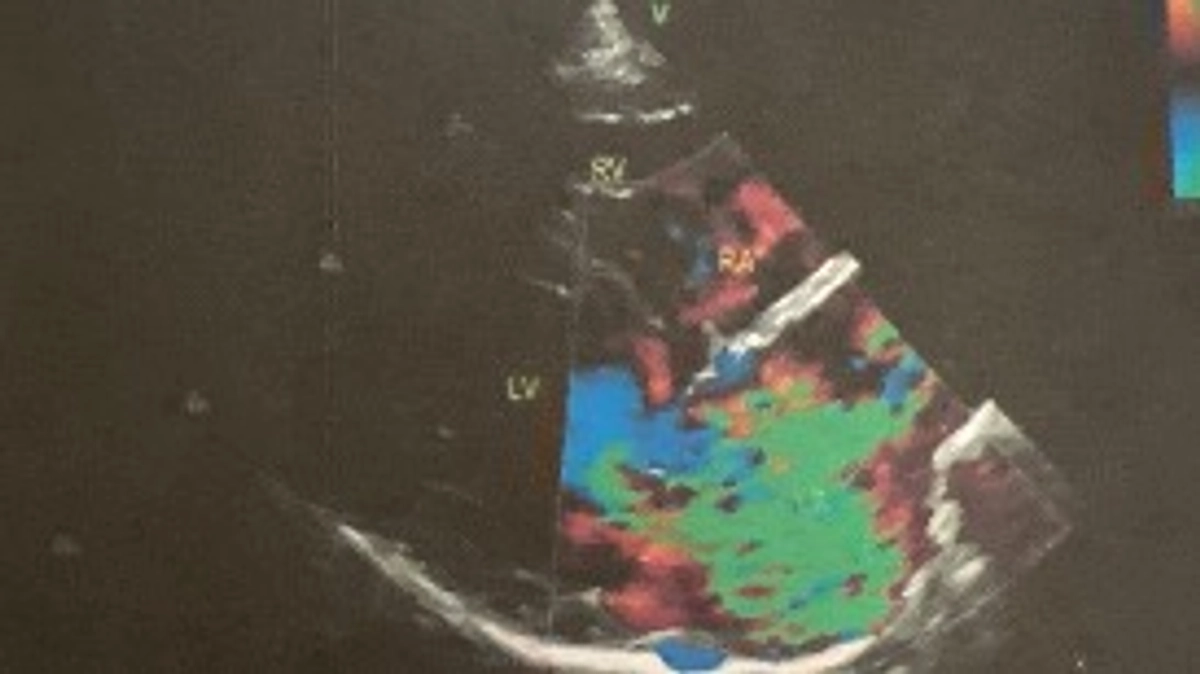

命の危機が迫っています!僧帽弁閉鎖不全症・三尖弁閉鎖不全症